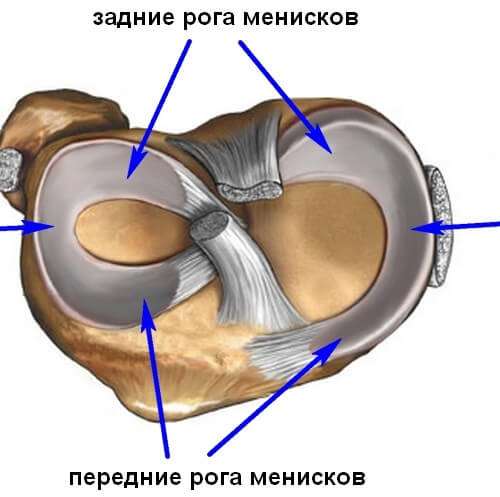

Анатомические изображения менисков и коленного сустава

Раздел: Иллюстрированные советы